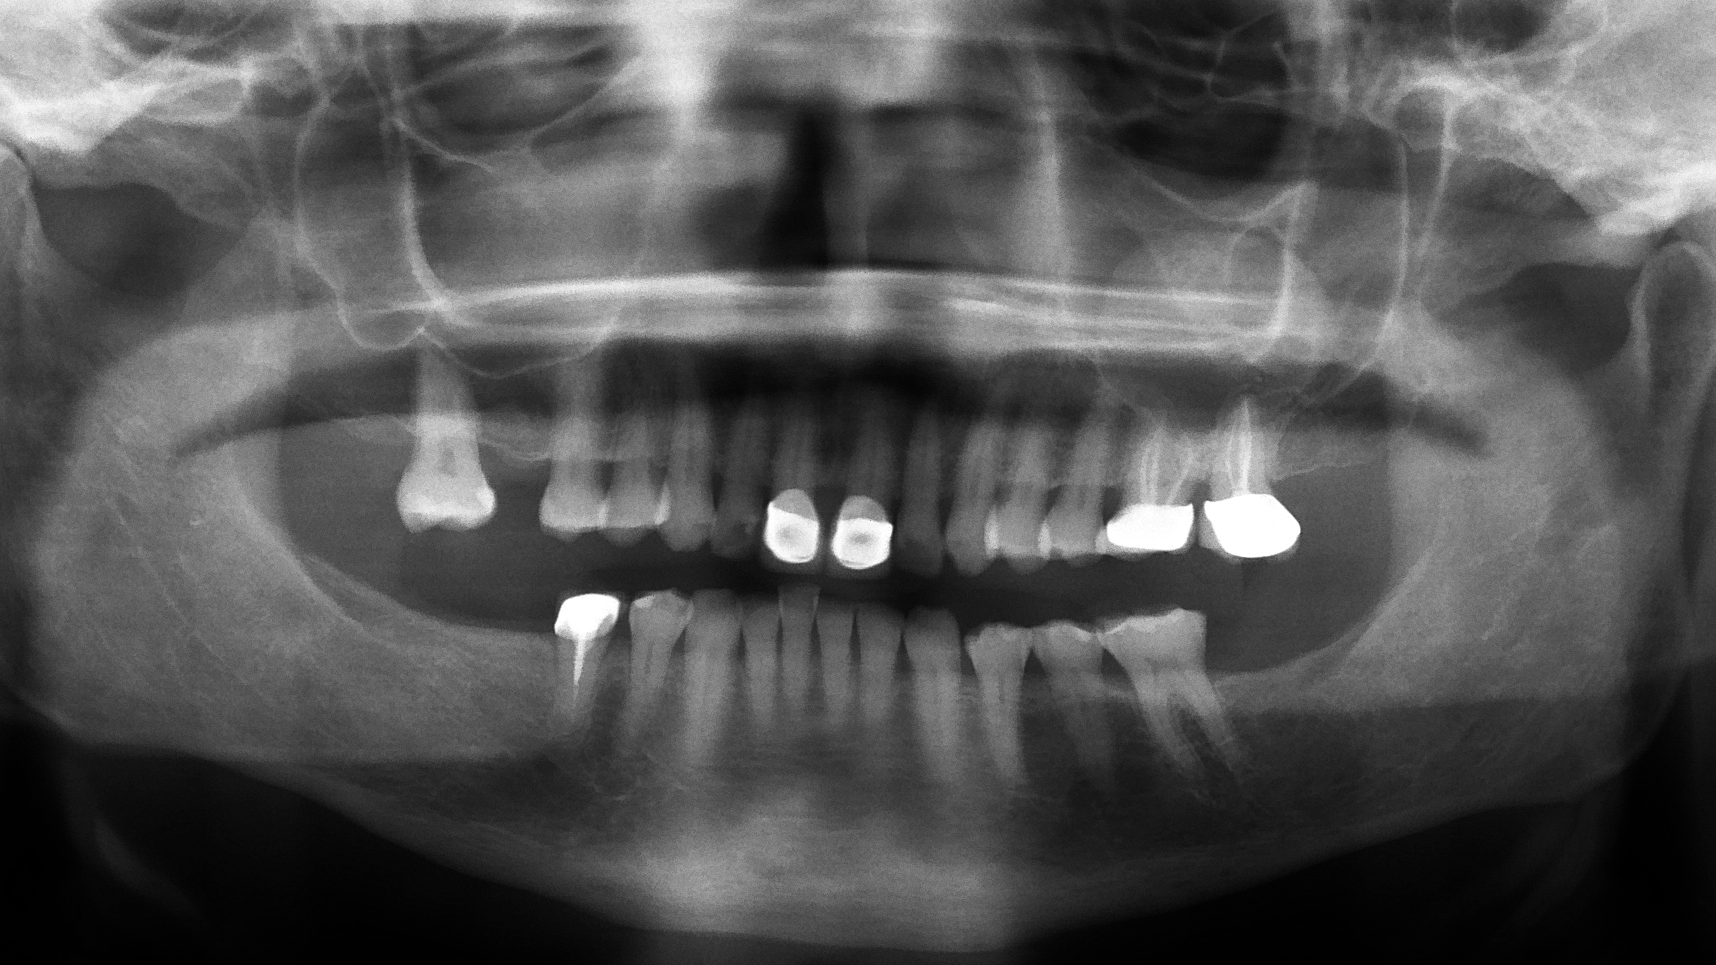

It is reported that pseudocysts are found in up to 14% of the population.2 Antral pseudocysts are formed by the inflammatory serous exudate accumulating below the sinus membrane and causing a dome- or sessile-like elevation with a faintly radiopaque and well-delineated dome appearance. Although the cause has not been definitively confirmed, antral pseudocysts have been associated with allergies, respiratory and viral infections, and forced-air heating (figure 1).2

The clinician may confuse the antral pseudocyst with a nonodontogenic cyst, an odontogenic cyst (such as a dentigerous cyst, an odontogenic keratocyst, or a residual cyst), or an inflammatory lesion (such as a radicular cyst, an odontogenic tumor, or a nonodontogenic tumor). When viewing the finding on a panoramic image, the next step is to acquire a periapical image of the area in question. The vitality of any teeth in the area should be determined, and unrestored teeth without evidence of pulpal or periodontal disease should test vital if the area in question is an antral pseudocyst of nondental origin and should allow the elimination of other entities in some cases. However, when the location or the presentation of the entity is in question, further testing is usually needed, such as advanced imaging, biopsy, or fine needle aspiration. Referral to an oral surgeon or an otolaryngologist would be appropriate.5,6